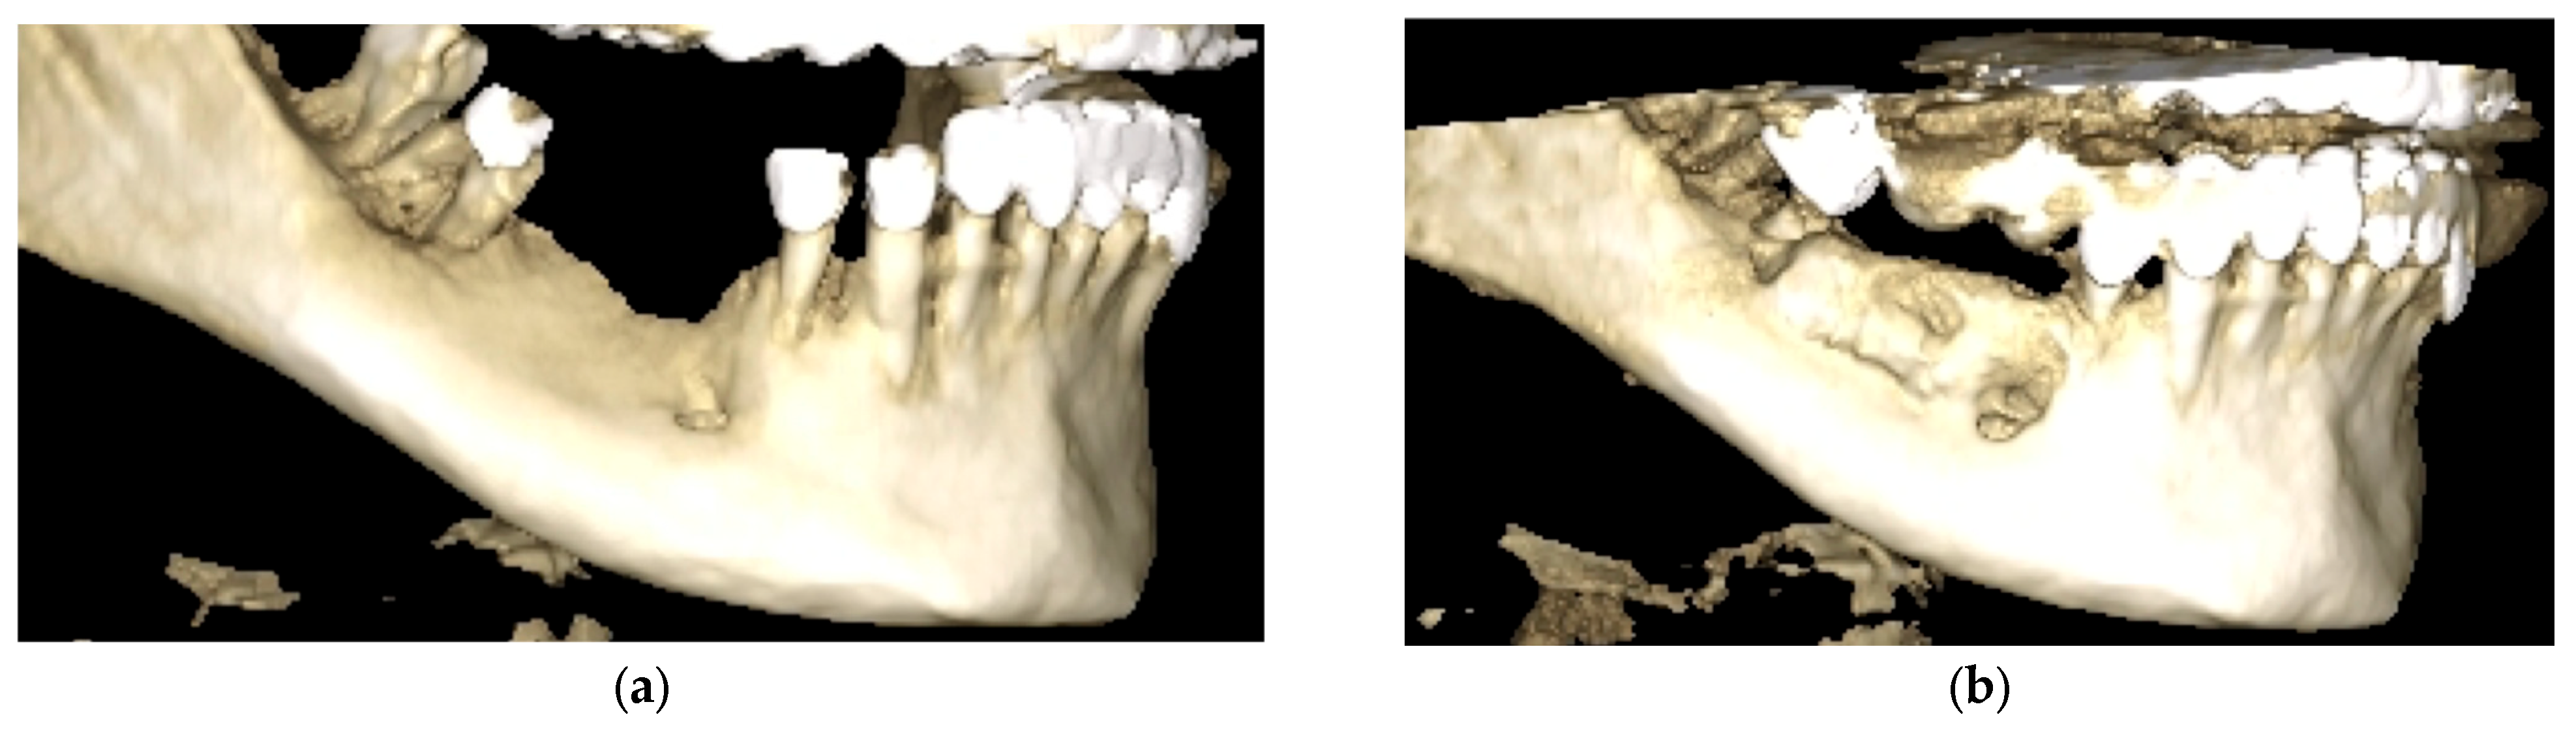

Three-dimensional renderings were also employed to evaluate volumetric changes and spatial morphology of the mandibular bone (Figure 13). Before augmentation, the 3D reconstruction revealed severe horizontal and vertical atrophy in the posterior mandible. The cortical outline was thin, irregular, and interrupted, with insufficient bone volume for implant placement (Figure 13a).

Postoperatively, the augmented ridge exhibited continuous, well-defined cortical borders and substantial volumetric gain in both horizontal and vertical dimensions. The reconstructed segment appeared anatomically stable and suitable for implant placement (Figure 13b).

Figure 13. Three-dimensional CBCT reconstructions of the posterior mandible. (a) Preoperative rendering showing extensive alveolar resorption and cortical discontinuities. (b) Six-month postoperative reconstruction illustrating volumetric restoration and cortical continuity.